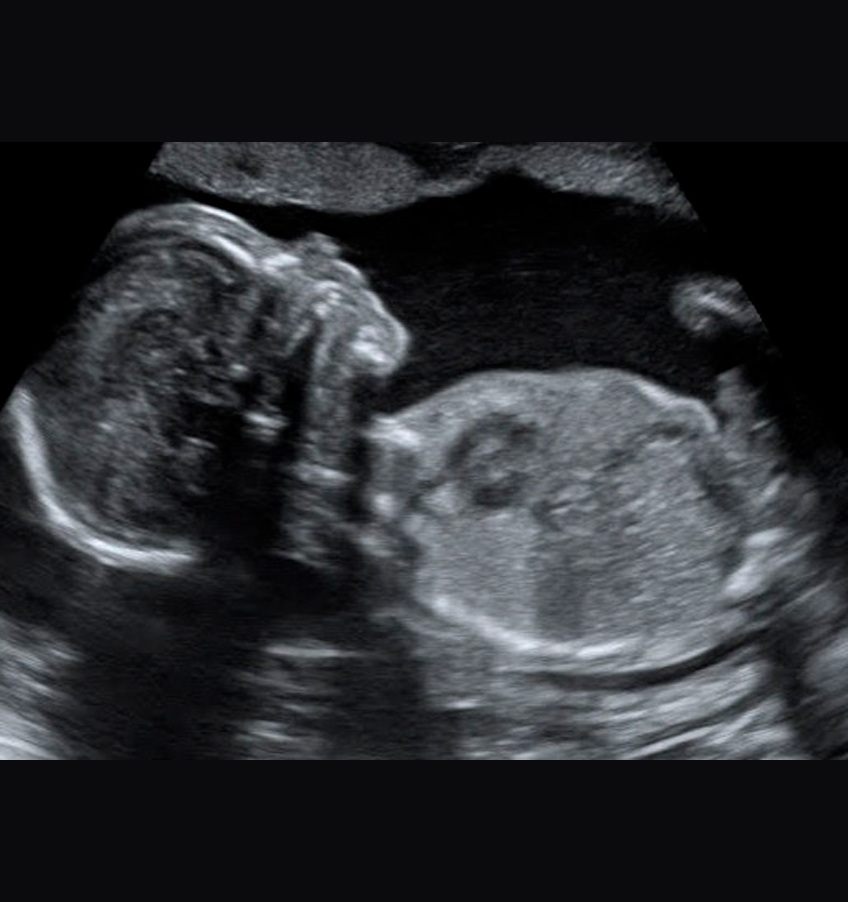

ULTRASOM DE ALTA RESOLUÇÃO